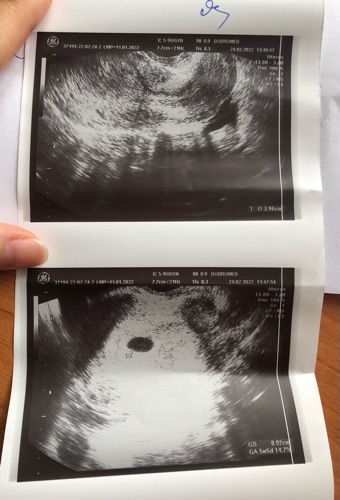

Dạ em đã đi khám lại, thai vào tử cung rồi ạ, không phải thai ngoài ạ. Cảm ơn bác sỹ!

07/03/2022